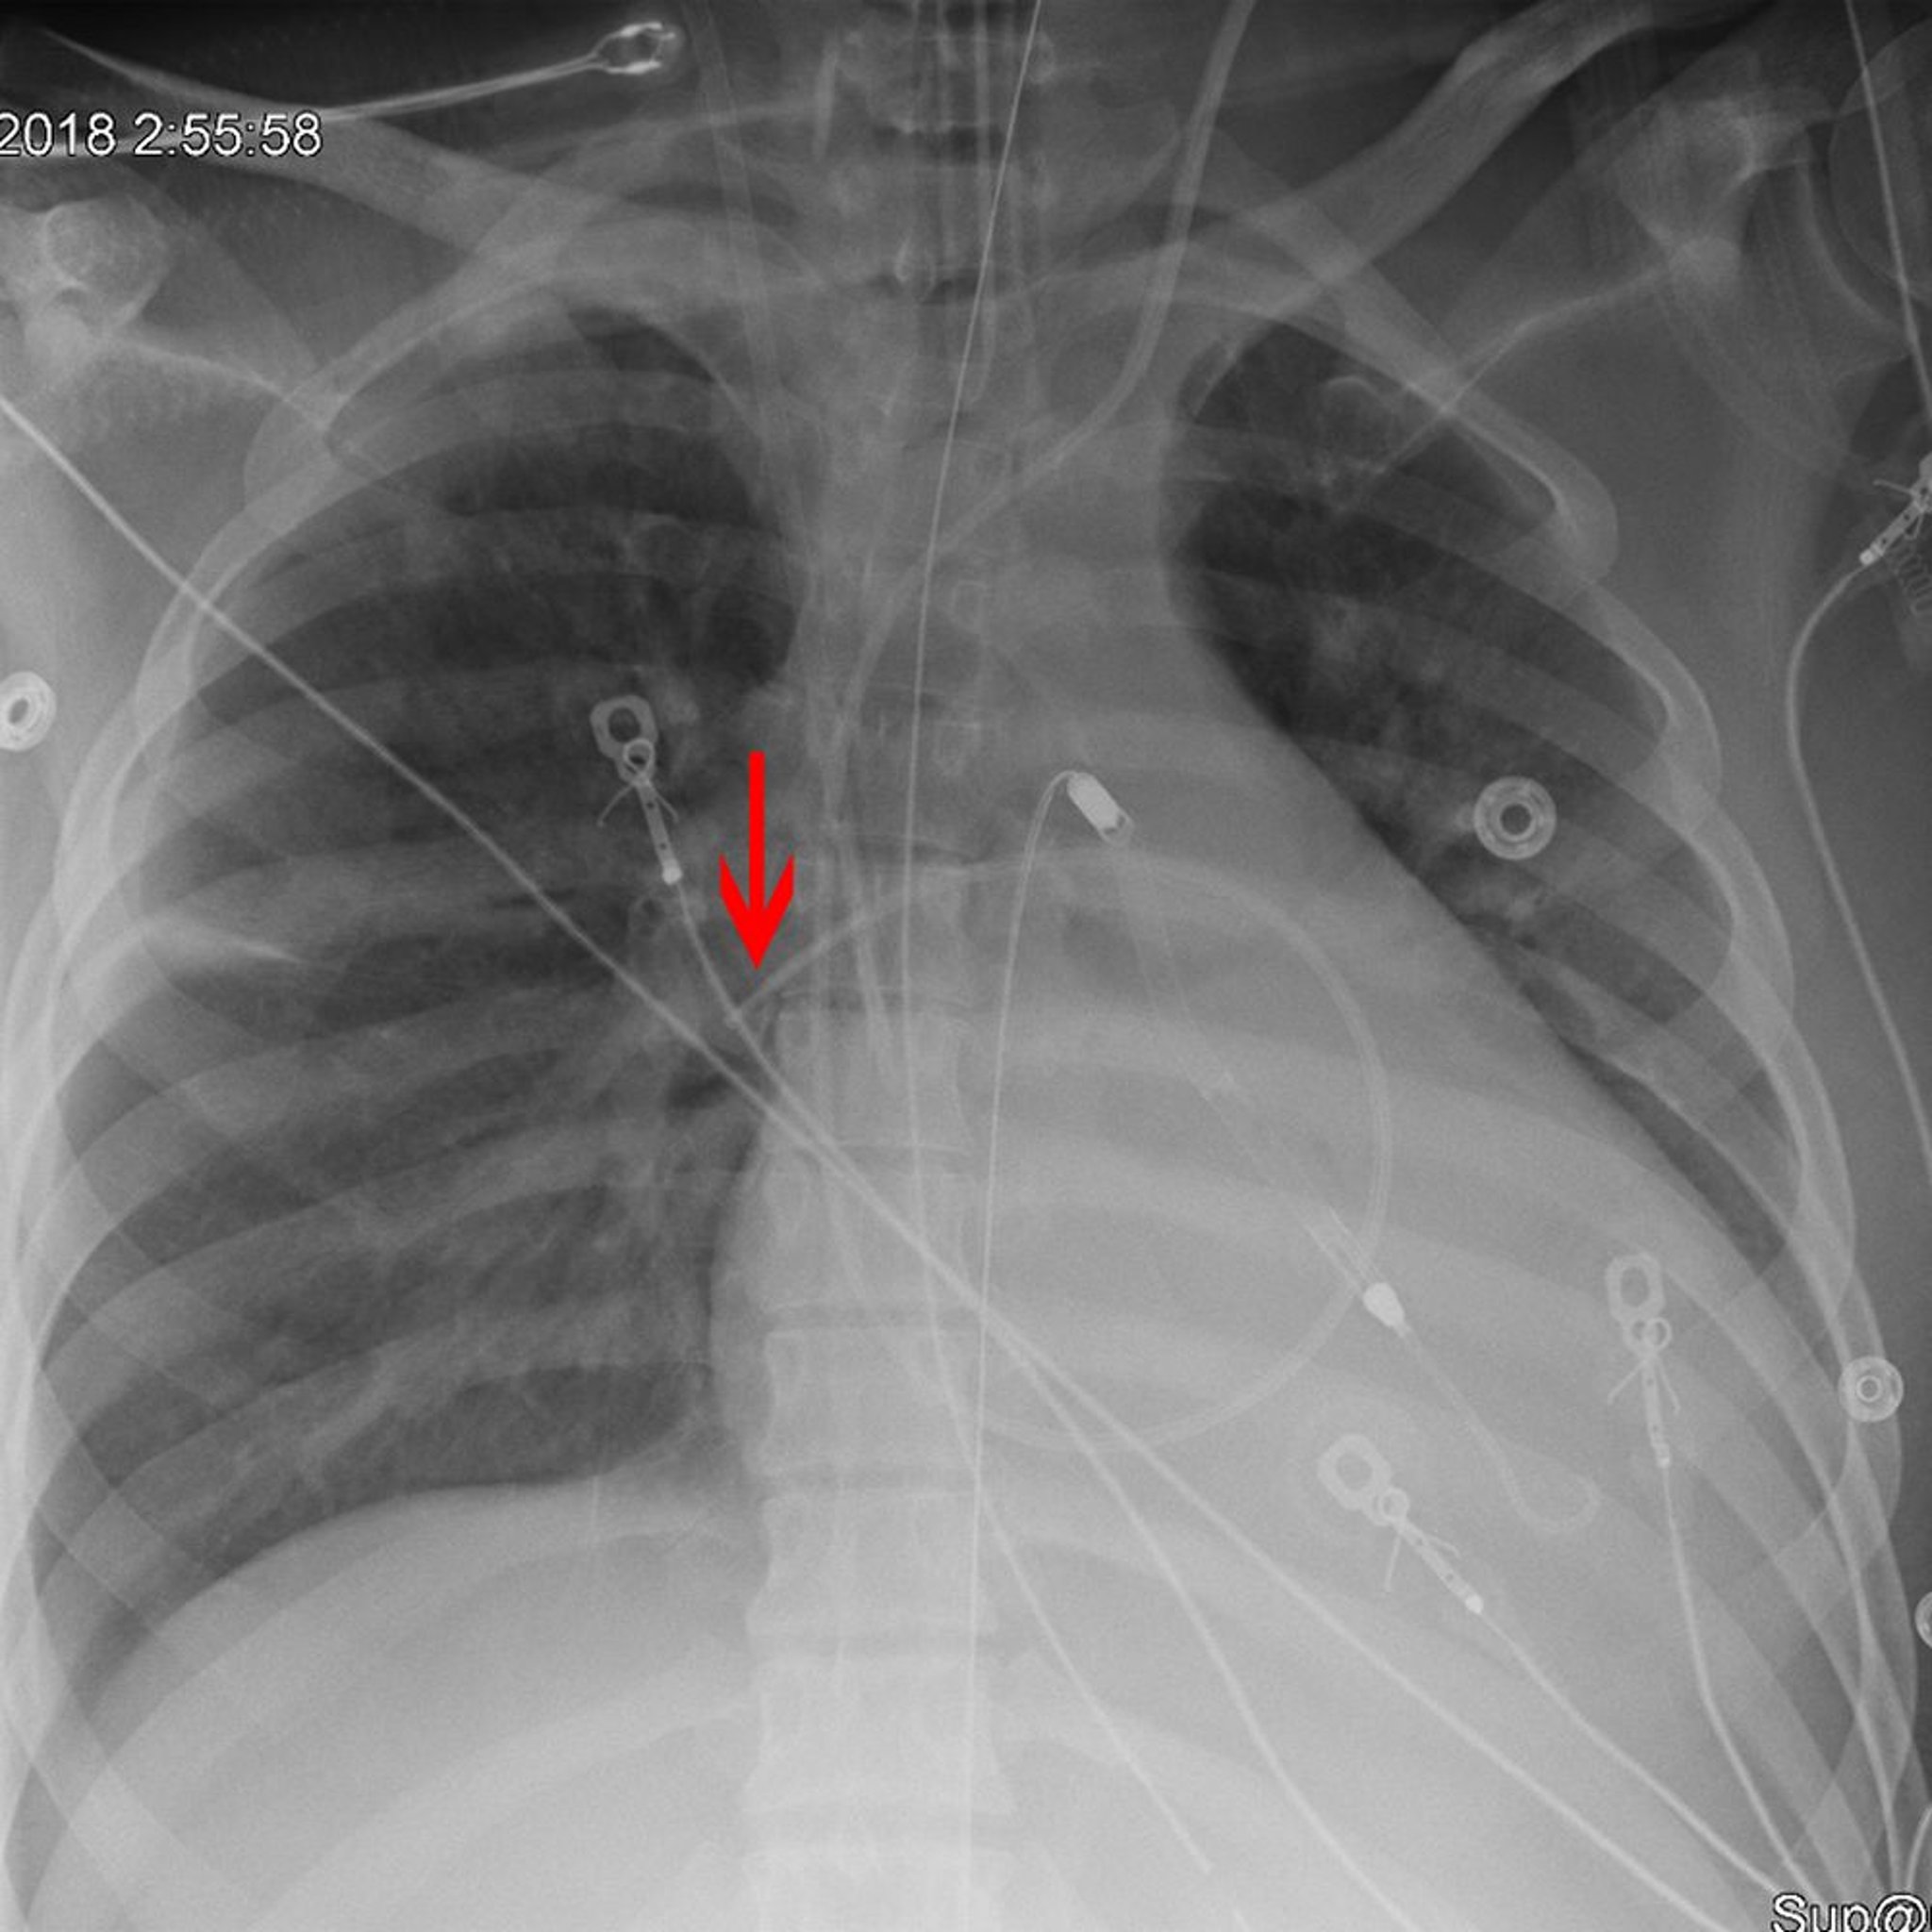

Radiographie montrant le positionnement correct d'un cathéter de Swan-Ganz

La flèche pointe vers la pointe d'un cathéter de Swan-Ganz (artère pulmonaire) placé de manière appropriée dans l'artère pulmonaire droite.